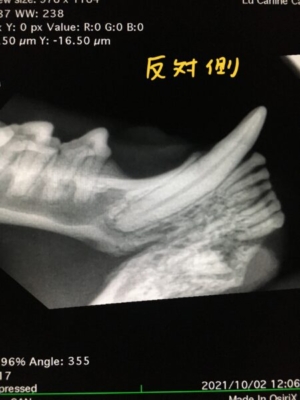

歯科用レントゲンで撮影すると、実は下顎の犬歯は抜けておらず、途中で折れた歯根が残っている事がわかりました。

猫の歯が途中から折れてなくなっているように見えるときは、吸収病巣という病気で歯茎から歯が溶けてしまう場合と、強い力が加わって折れてしまう破折の場合があります。今回は斜めに折れている事からなんらかの外傷で折れた可能性が高いと判断しました。

また、歯茎が赤くなっていた第一前臼歯は歯槽骨(顎の骨)が吸収されており、抜歯が必要な歯周病となっていました。下顎犬歯の破折から歯槽骨の吸収が起こり、隣の第一前臼歯まで進行したと考えられました。